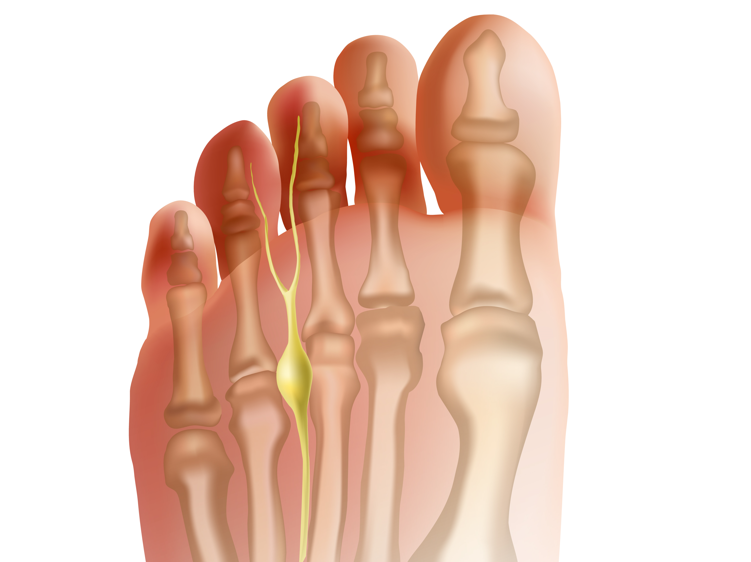

| Neuroma | A tumor involving a nerve. | ![]() |